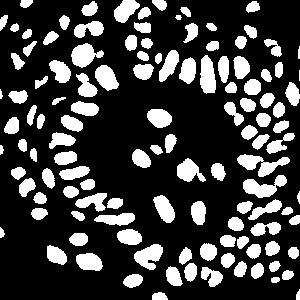

(a) image

(b) round 1

(c) round 2

(d) round 3

An example is shown in Fig. 2 to illustrate the masks in different rounds of self-training. The foreground nuclei annotation (green pixels) is kept unchanged during the iterations while the background area (pixels in black) grows up gradually. In the third round, the background has high accuracy and the ignored pixels (orange) are almost all nuclei.